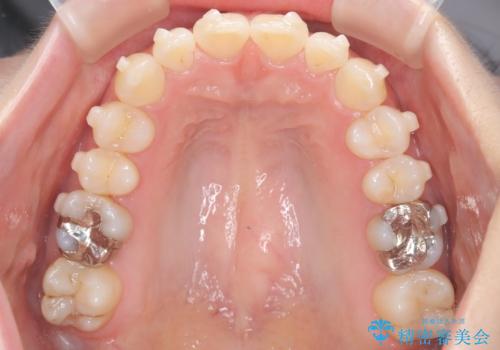

インビザラインで整えた前歯の歯並び

- 患者様は、上下前歯の歯列不正(ガタガタ)を主訴としてご来院されました。治療計画として、透明なマウスピース型矯正装置「インビザライン」を使用し、約2年の期間を見込んで前歯部の歯列を整える方針を立てました。特に下顎前歯に歯肉退縮のリスクがあるため、治療中にIPR(インタープロキシマルリダクション)を行い、歯間を適切に削ることで、過度な圧力を避け、歯肉退縮を防ぎながら配列を進めました。治療は慎重に進め、最終的にきれいで整った前歯の歯並びを目指しました。